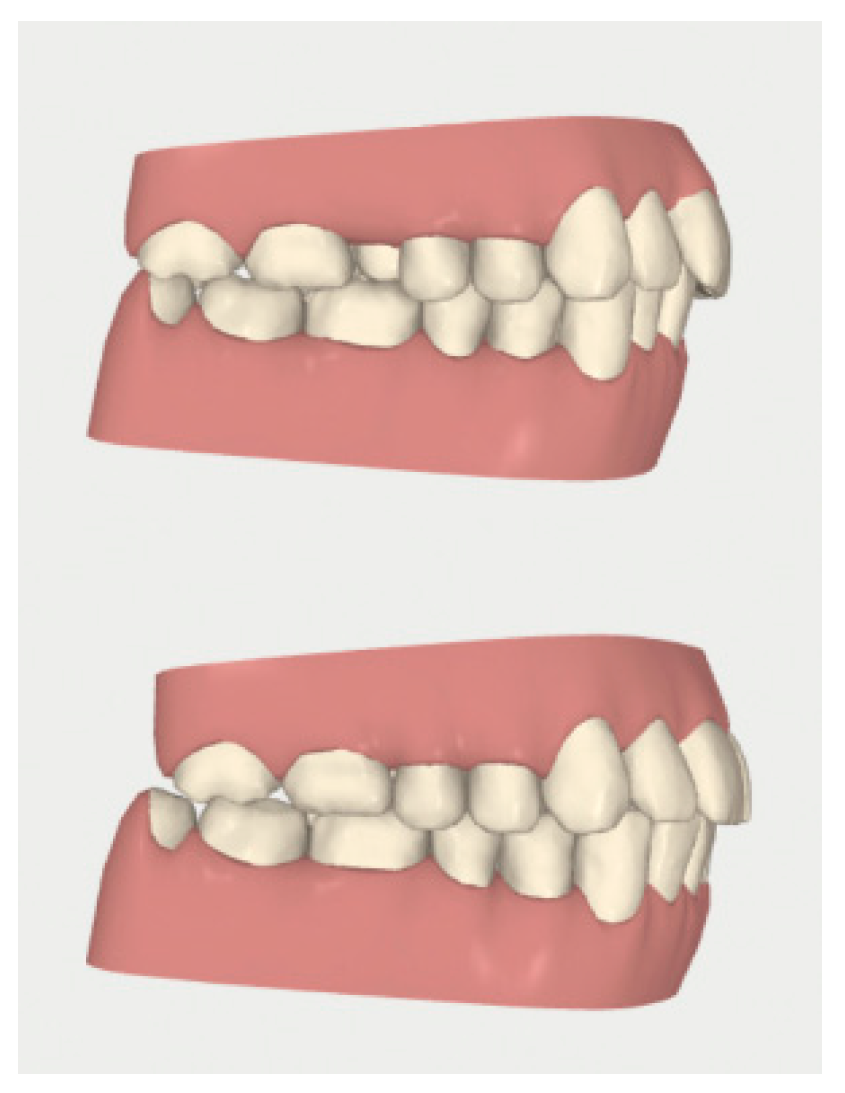

2.2. Orthodontic Planning

2.3.1. Example—Anterior Open-bite

2.3.2. Example 2—Extraction Space Closure